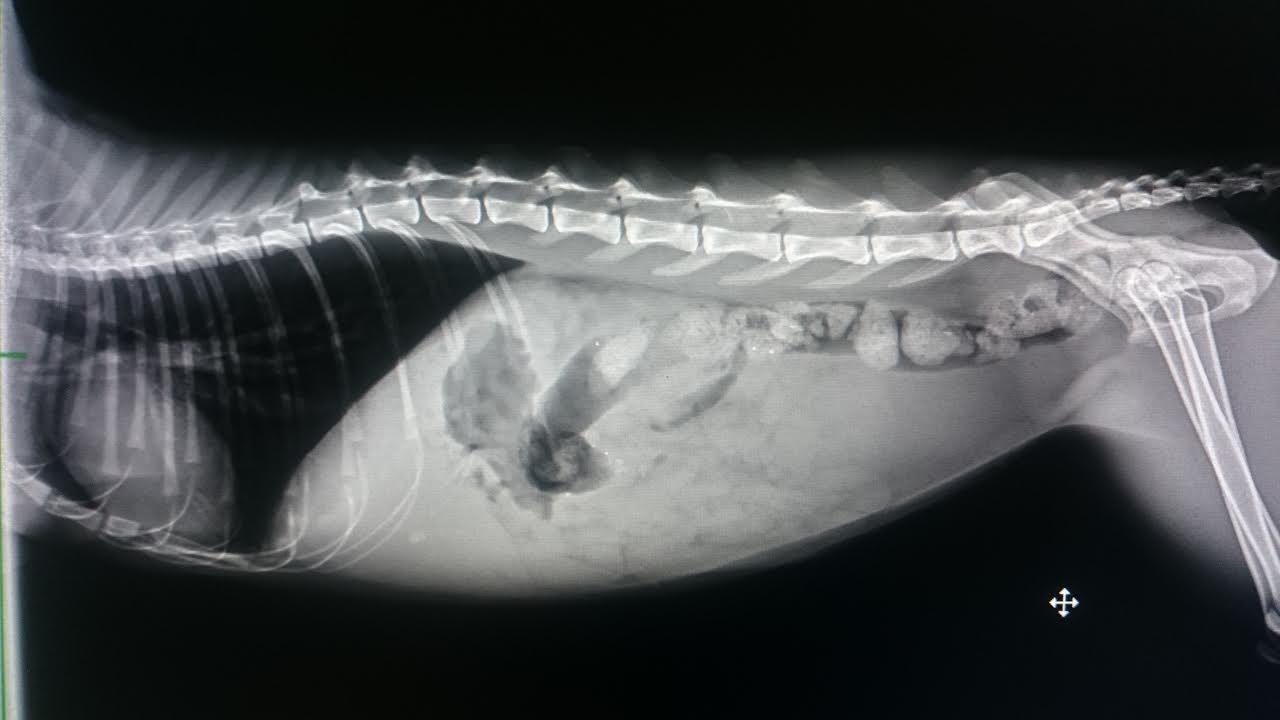

鐵蛋有貧血問題,肝腎指數皆偏高

且腎功能不全(多尿)

以及腎衰、膽結石,

1. 貧血,肝腎指數偏高,腎功能不全(多尿)